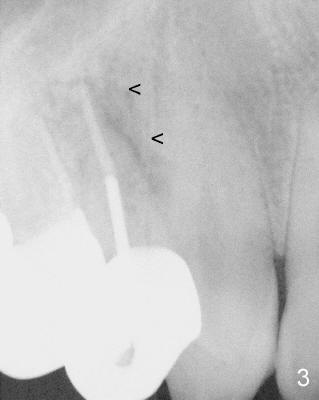

A 68-year-old male patient presented to office in March 2011 with chief complaint "upper right tooth is not comfortable". Clinical exam shows missing teeth: #13,14,30, and 31, replaced by removable partial dentures. The tooth #5 has mild mobility and percussion. Pocket depth is within normal limit. X-ray shows no significant finding (Fig.1,2). Three months later, he returned with chief complaint "The tooth has swelling". It appears that there is exostosis on buccal aspect of upper teeth. There is no erythema or tenderness on buccal mucosa around the tooth #5). But X-ray shows periradicular radiolucency (arrowheads in Fig.3,4). Cone Beam CT was recommended to confirm diagnosis of root fracture. Approximately one month later, abscess developed with fistula formation. Symptoms were controlled by taking Amoxicillin. On August 2, 2011, the patient returned for prophylaxis. The fistula was present (arrowhead in Fig.5). Gutta percha #30 was inserted into the fistula. PA was taken. The point of the gutta percha (blue arrowhead in Fig.6) points to enlarged periradicular radiolucency (black arrowheads). Deep pockets were in distobuccal and lingual. Decision was made to extract the tooth. Fig.7 shows the socket immediately extraction. The buccal plate is perforated. The septum (*) is not intact. Cracking sounds were heard during extraction. In fact the lingual root is obliquely fractured with exposed post (Fig.8: *). There is another cracking line from the buccal root to the lingual one (arrowhead). In brief, the earliest sign of root fracture is nonspecific. It should alert us to its suspicion.